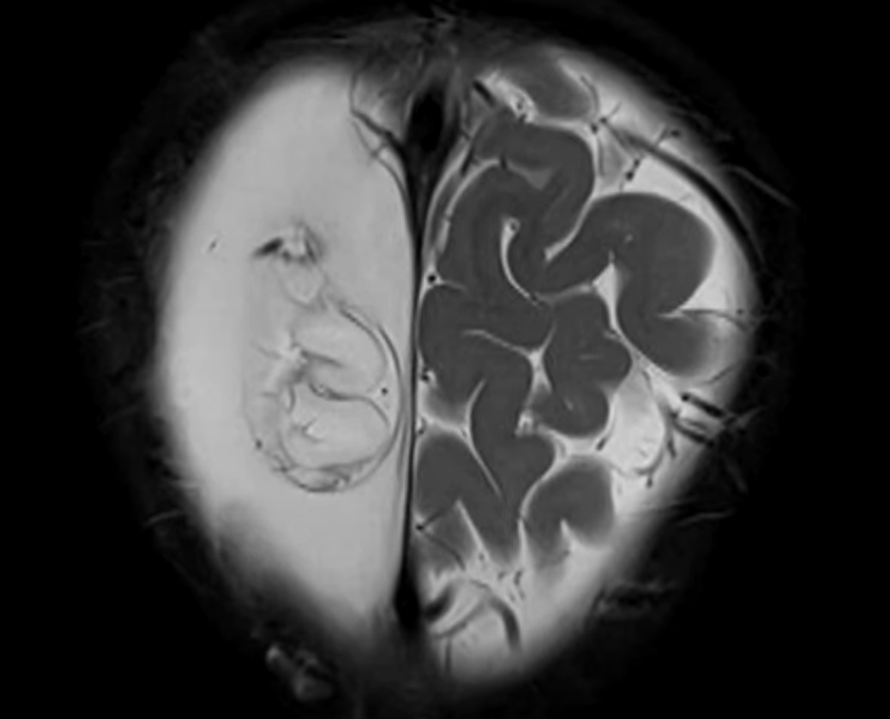

小雪兒的媽媽Amy在無綫節目《東張西望》中受訪表示,女兒獲院方安排接受重置頭骨手術。(《東張西望》畫面)

她又指目前還要面對其他問題,之前取出的骨頭儲存於雪櫃,「已冇晒生命」直接可以形容為「死骨」,再填補原位純屬保護作用,該塊骨可能會被身體當作外來物排斥,所以面對極大風險。另外,小雪兒目前腦部情況變壞,最新腦素描影像報告,「右邊紋路可能清晰,左邊則呈一片空白」,顯示左腦萎縮,故需要盡快手術。